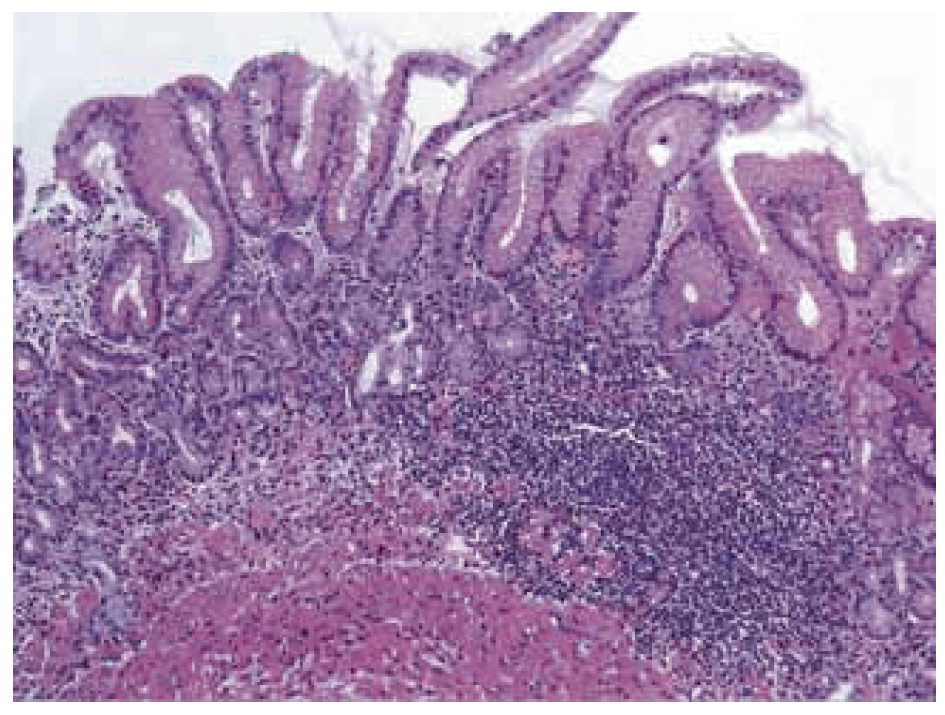

2. Fig. 2. Stomach carcinoid: a cluster of neuroendocrine cells in the lamina propria of the mucosa against the background of autoimmune atrophic gastritis with areas of intestinal metaplasia Stained with hematoxylin-eosin [5]. | |